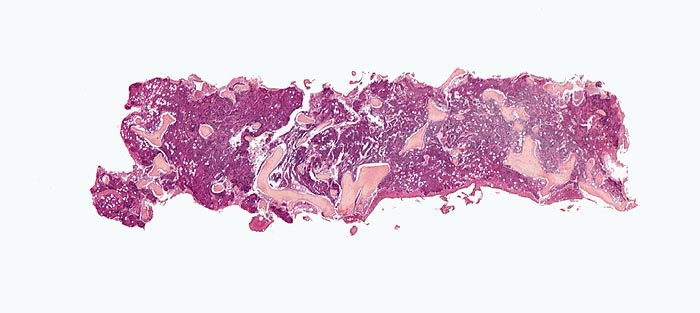

Die Erkrankung ist charakterisiert durch Knochenmarkfibrose, Hepato-Splenomegalie und extramedulläre Blutbildung. Diese findet sich am häufigsten in Leber und Milz, seltener in Lymphknoten, Nieren, Nebennieren, Dura mater, Gastrointestinaltrakt, Lunge, Mamma oder Haut. Blut und Knochenmark sind immer involviert. Die Krankheit entwickelt sich über ein initiales präfibrotisches Stadium mit hyperzellulärem Knochenmark zum fibrotischem Stadium (vorliegendes Präparat). Das fibrotische Stadium ist gekennzeichnet durch eine Vermehrung von Reticulin- und/oder Kollagenfasern und oft einer Knochenneubildung (=Osteomyelosklerose). Die Zellularität des Knochenmarks ist dann vermindert und dilatierte Marksinus enthalten intraluminale Blutbildungsherde. Es besteht eine auffallende Proliferation von Gruppen bildenden atypischen Megakaryozyten.

• Osteosklerose: verplumpte und breite Knochenbälkchen.

• Kollagenfibrose.

• Dilatierte Sinusoide mit intrasinusoidaler Blutbildung.

• Vermehrung von atypischen, in Gruppen liegenden Megakaryozyten mit abnorm lobulierten Kernen.

• Retikulinfaserfibrose des Marks vorhanden aber in der HE Färbung schwierig quantifizierbar.